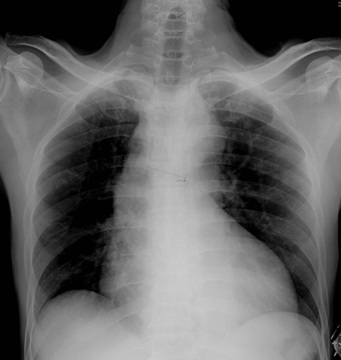

Fasceitis Necrotizante

Antonio Alvarado Armuelles, Alonso Bósquez Barría